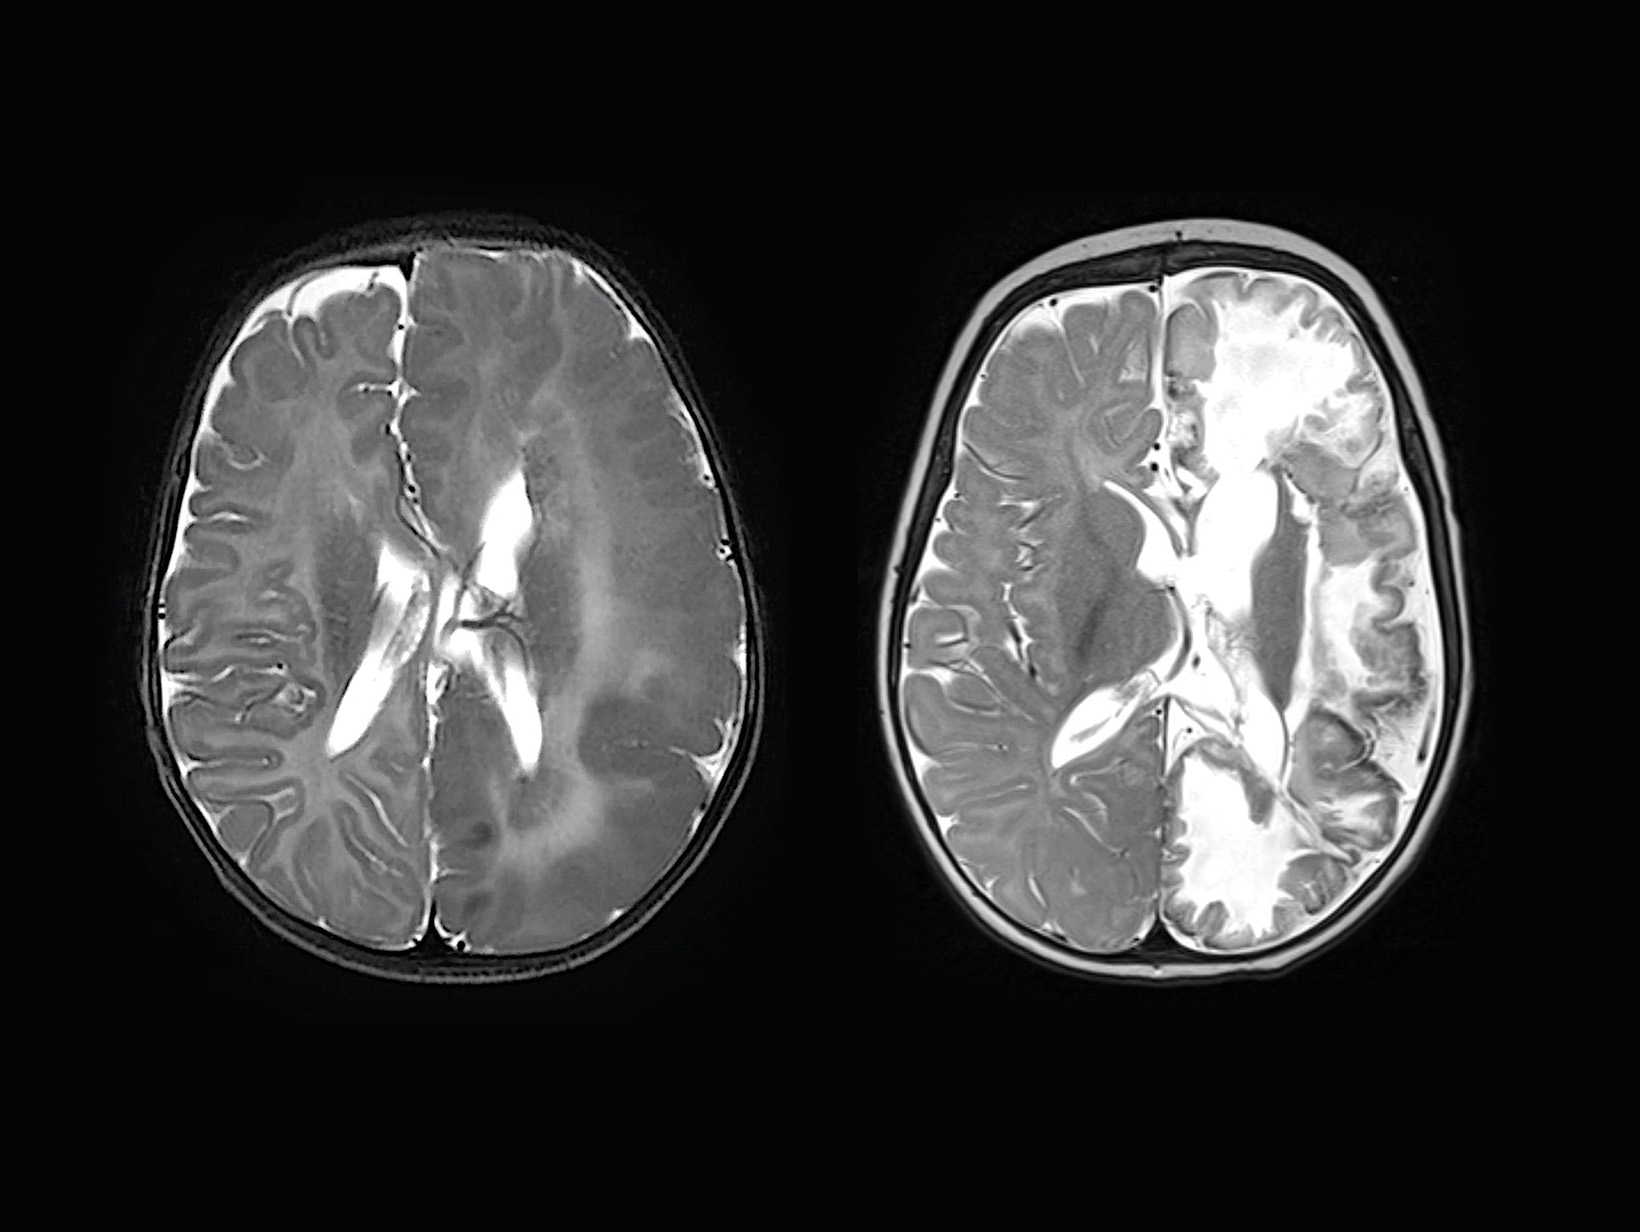

If the MRI scan were a piece of art rather than a medical image, the two halves of Maryam’s brain could have been rendered by entirely different artists. Her right brain hemisphere was like a pencil sketch, a work of realism; the brain folds looked clear and sharply defined, with the grey and white matter separated by distinct borders.

Her left brain hemisphere, however, was an abstract watercolour. The brain ridges looked puffy and haphazard, with the grey and white matter blurring together, as though too much water in the brush had caused the paint to bleed.

The left hemisphere of Maryam’s brain was also noticeably bigger. She was transferred to SickKids, where doctors diagnosed Maryam with hemimegalencephaly (HME), a rare birth defect where one side of the brain is abnormally large. The brain hemisphere’s function is so disturbed, and the neurons so disordered, that it is effectively capable of only one thing: causing seizures.